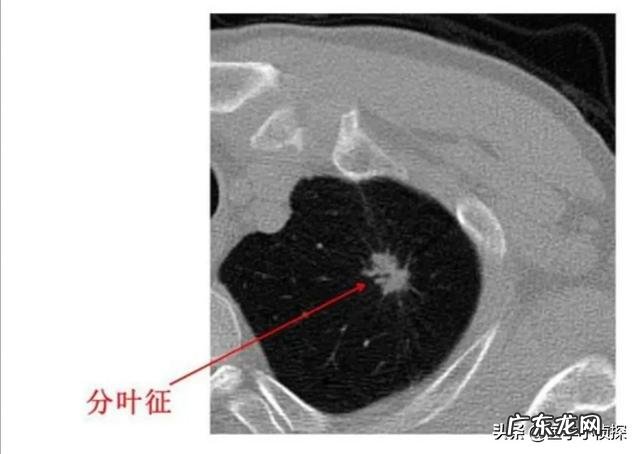

而且拍片发现肺结节 , 本身不能说我们得了什么病 , 因为肺结节只是我们影像学上的一种表现 , 并不代表这个结节具体会是个什么东西 。只是对于我们正常人来说 , 不应该有结节 , 因此结节的出现肯定代表我们的肺部有病变 , 但具体它是什么 , 是良性的 , 还是恶性的 , 需要进一步的来区分 。只不过 , 一般情况下 , 在影像下我们统称这些都叫肺结节 。

假如你胸部CT检查出肺结节 , 重点关注报告单上这些内容 , 基本上不用过于担心肺结节最后会发展为晚期肺癌!